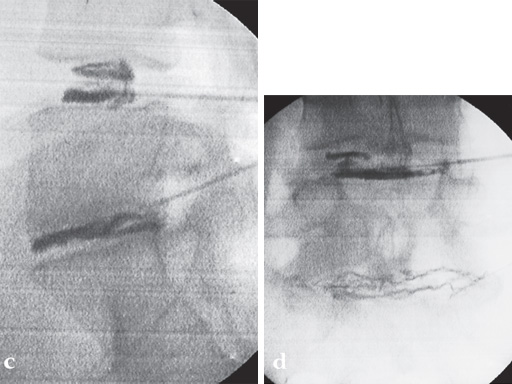

A 37-year-old female (65 kg and 170 cm tall) who suffered from back (L5/S1) and leg pain without neural compression for 2.5 years. She had a full range of conservative treatment and rehabilitation without benefit and reports a significant improvement in symptoms and function following surgery. She has returned to work with minimal restrictions in ongoing activities.

Postoperative pictures.